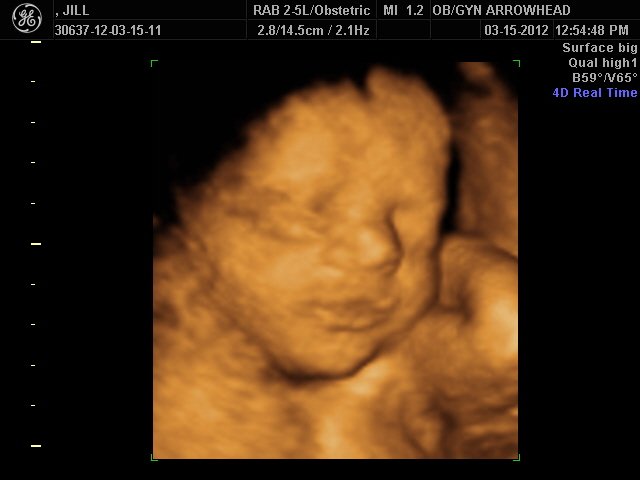

We offer complimentary 3D/4D Ultrasounds to all our OB patients around 30 weeks! The following photos are some examples of our work, shown with permission from our patients.